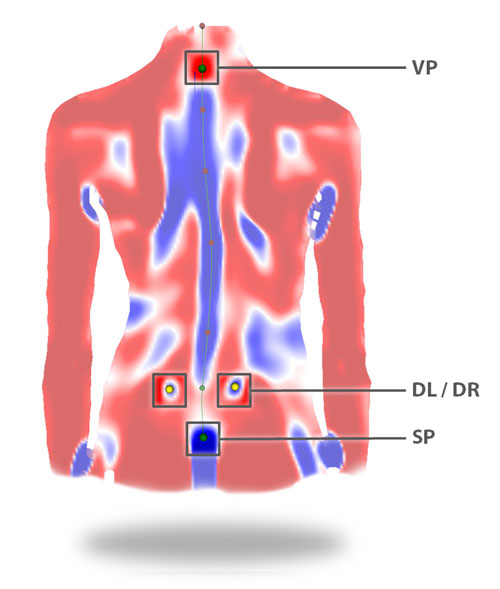

После обследования получается трехмерная или четырехмерная модель позвоночника и таза пациента.

- 3D-Реконструкция поверхности спины и позвоночника без рентгеновского облучения